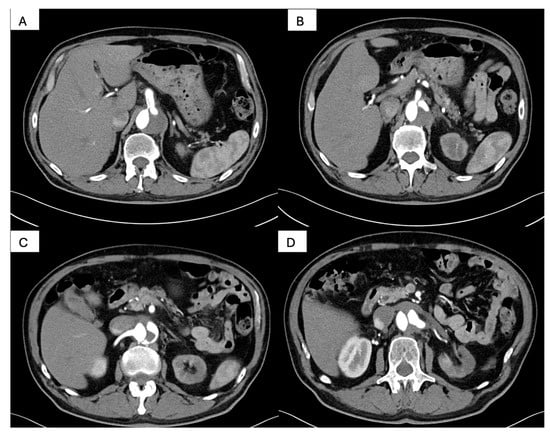

2. Case Report